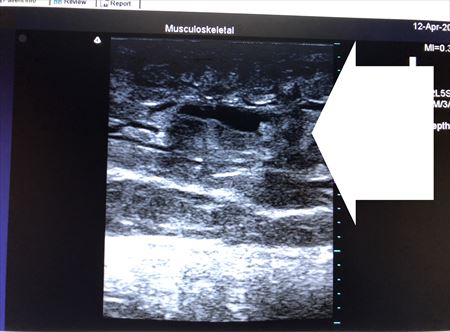

ここではふくらはぎの術中変化を見てみましょう。

上の画像の部分の皮下脂肪層をつまんでみましょう。